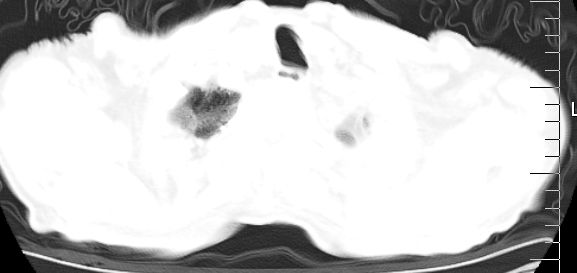

标题: CT10141:男、84岁,咳嗽、咯血1年。 [打印本页]

标题: CT10141:男、84岁,咳嗽、咯血1年。

支持左侧中央型肺癌伴下叶肺不张\\纵隔淋巴结转移.左侧包裹性胸腔积液\\心包积液.左侧少量胸腔积液..慢性支气管炎伴部分间质纤维化.

支持:左侧中央型肺癌伴下叶肺不张\\纵隔淋巴结转移.左侧包裹性胸腔积液\\心包积液.左侧少量胸腔积液..慢性支气管炎伴部分间质纤维化.另:支气管分支根部明显阻塞 狭窄,内膜凸凹不平,提示内膜增生物。

咯血病史较长,左肺下叶实变,体积未明显缩小,隐约可见血管影及坏死阴影,双肺门及纵隔淋巴结增大,心包增厚积液,纵隔右移位,单侧胸腔积液,首先考虑:大叶型肺泡癌伴纵隔心包转移。

左下中央型肺癌伴阻塞性不张,肺炎,左侧包裹性胸腔积液\\心包积液

左肺中心性肺癌并左肺下叶肺不张,纵隔淋巴转移、同侧胸腔及心包积液(转移)。